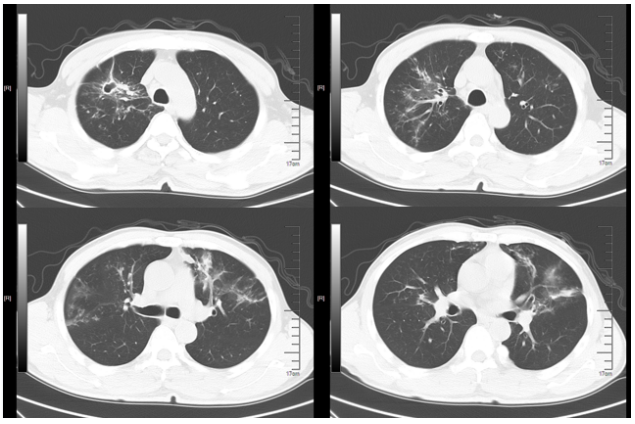

新冠病区诊治过程:鼻导管吸氧;阿兹夫定5 mg qd抗病毒、莫西沙星0.4 g qd抗感染,丙球10 g qd,地塞米松6 mg×2 d,之后予甲泼尼龙40 mg bid抗炎,低分子肝素钠5000单位ih q12h抗凝等治疗。2023年1月10日胸闷气急症状加重。血气分析(FiO2 41.0%):pH 7.39,PaO2 35.6 mmHg,PaCO2 34 mmHg,氧合指数87 mmHg。胸部CT(2023年1月10日,我院):双肺斑片影,符合病毒性肺炎,且较2023年1月6日明显加重(图1);双肾萎缩;双肾结石。

图1  患者胸部CT

1月17日复查胸部CT:双肺磨玻璃影较前有所吸收(图2)

图2  复查胸部CT(2023-01-17)

转入我科后患者体温热峰似乎有所下降,但仍有低热。1月27日复查胸部CT可见新冠肺炎病灶吸收、空洞形成,其中见小结节。支持真菌感染(图3)

图3  复查胸部CT(2023-01-27)